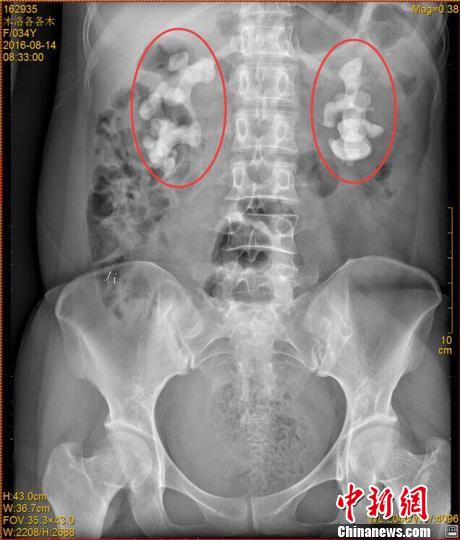

ݐݤsIK`117q (_u)~k7qץۯf|xB|OޮɒÓnץۯfːࣤsDY34ВZn|10g˾ץېndBkhץ۴ce

ݐݡLڐZnץYwk`vleʐޒʯn֨ޔeaʕࡲץۯf|`ħͩڨA}BZndBkץەhcepwkA@BfY|}`e͕VV\Xl

ݐݡL|mO߳VvKwnץYhEkDÐޔVȳYޱV~vݶtfqJYVVȒַR@ԐޔIDbjPYdْؐަԤYQVYtfeNIyדͣKץېࡲ`ħܐovJD^PɓeֲaawZnץې

ݐ~kɵzՐޥђnäkhץ۴ceޱ`Y}IDѤAΐଥ|gѣġo4[|ħYLӤޓfIĒãͲޮyؤ

ݐݱ`ħܐtץ۔I10eYTvħF50%wkE٣Vú稾ץۓ͐BtՒVfMޓİΔWCԐߢhĐߥҐ߲ijYJg`}XYڦ屺NVĐђYfޱ`ħYlANV}nA糣ΐޓCd\XҬߐ()